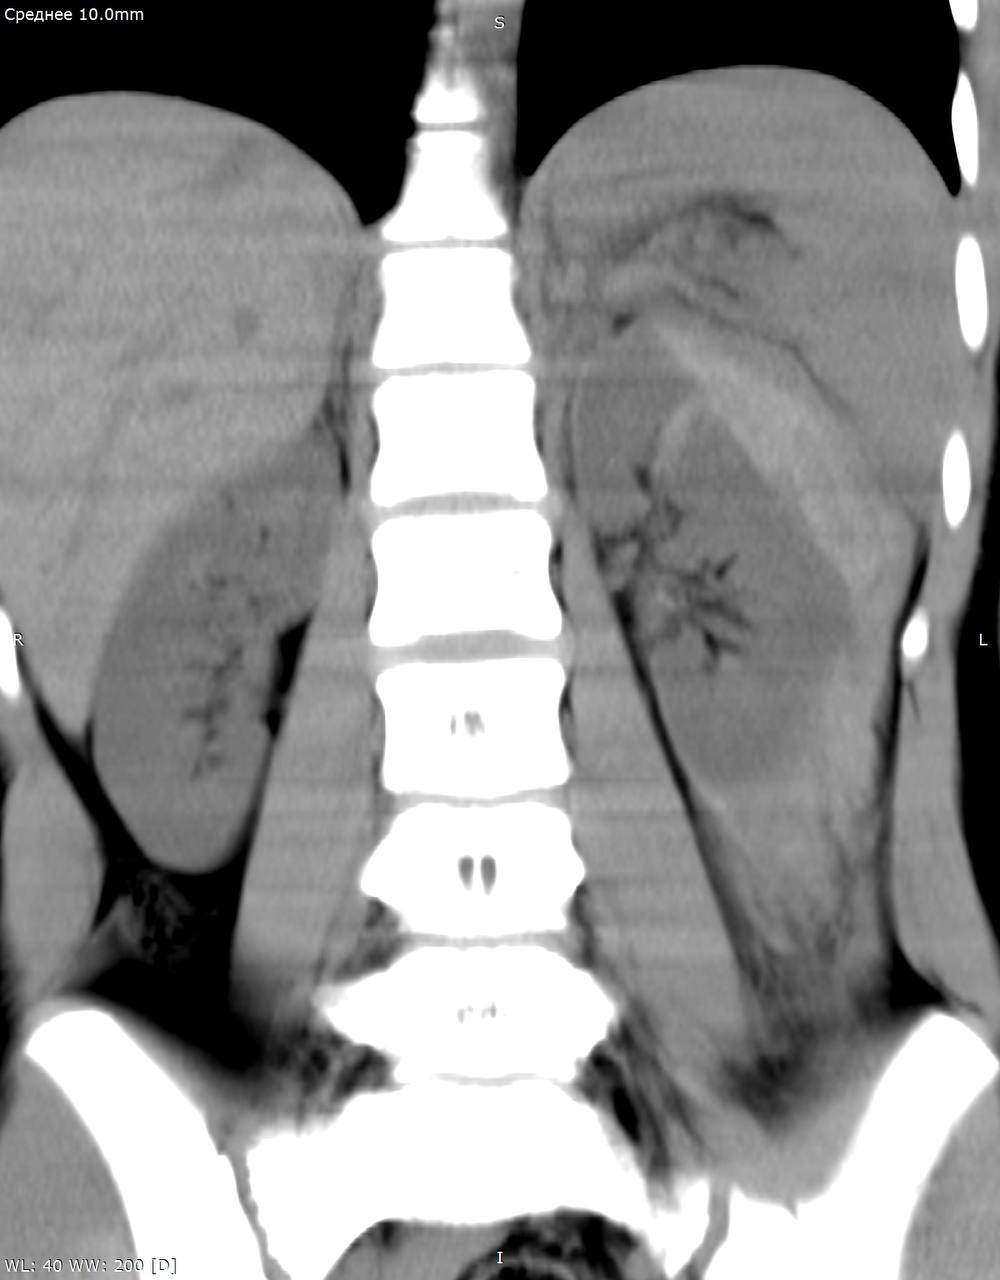

Девочка без почки

Девочка без почки 108 фото